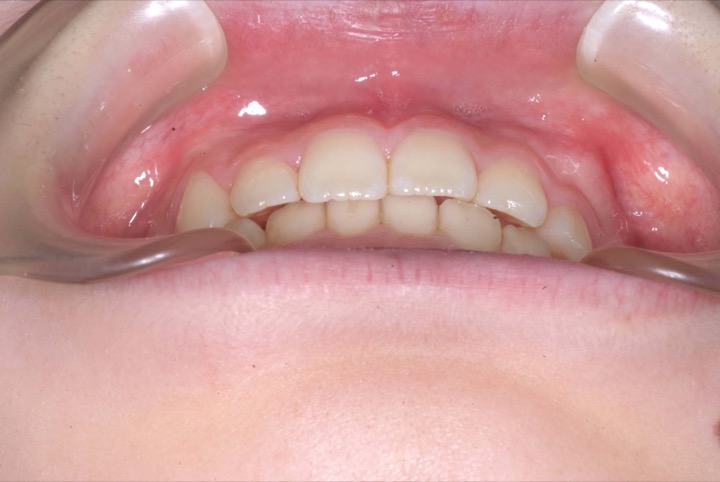

前期治療は、非抜歯の上、マウスピース型矯正装置(インビサライン・ファースト)で行いました。その後、歯列矯正用咬合誘導装置(マイオブレース)で舌位の改善を行いました。治療期間は5年1ヶ月でした。通院回数:37回。